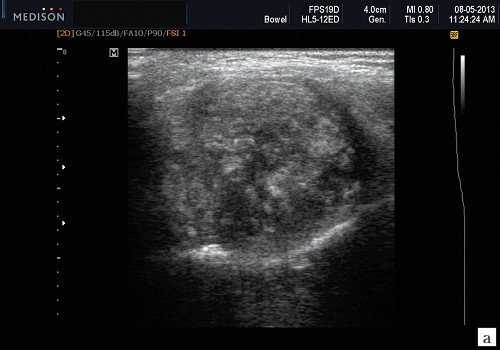

Сиаладениты - большая группа полиэтиологических воспалительных заболеваний СЖ (рис. 3). Первичные сиаладениты - сиаладениты, рассматриваемые в качестве самостоятельных заболеваний (например, эпидемический паротит). Вторичные сиаладениты - сиаладениты, являющиеся осложнениями или проявлениями других заболеваний (например, сиаладенит при гриппе). Эхографическая картина при разной этиологии малоспецифична. Этиология имеет клиническое значение в процессе определения тактики лечения.

Рис. 3. Сиаладенит правой поднижнечелюстной слюнной железы.